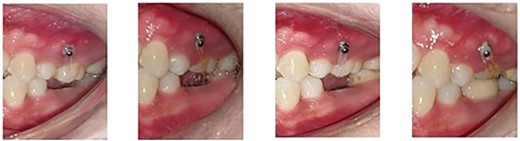

Following the placement of miniscrews, immediate loading was done with 100 g of intrusive force using a short power chain. The power chain was passed and engaged onto the composite button to ensure the forces are directed occlusally and there is no slippage. The patient was followed up at 4-week intervals and the power chain was replaced with one link, which was reduced at each appointment. After the first month, the dental implant was placed to replace the mandibular first molar. After 5 months of intrusion, the desired occlusal clearance was achieved and the upper and lower impressions were recorded (Fig. 2). For retention in the upper arch, the patient was given a clear vacuum retainer, while the crown was placed on the implant to prevent any relapse and to achieve good occlusion.

The intrusion process with placement of the prosthetic crown at the completion stage.

Intrusion of the maxillary left first molar without the requirement of any occlusal trimming or fixed orthodontic appliance.

Slight lingual inclination of the molar because of the length of the elastic chain being more on the palatal side.

Maxillary molar intrusion 4 mm above the occlusal plane (Fig. 3).